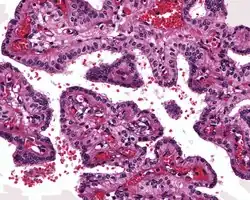

A high power image of an endolymphatic sac tumor showing clear cytoplasm in cuboidal cells lined up along papillae.

The microscopic appearance shows an unencapsulated, destructive growth, remodeling and invading bone. The tumor is arranged as simple, broad, non-complex papillary projections without large cystic spaces. The spaces are often fluid filled, have extravasated erythrocytes and/or inspissated material. The cells are cuboidal, usually single layered along the papillary structures, showing indistinct cell borders. The nuclei are round and hyperchromatic.[1][3][10][11]